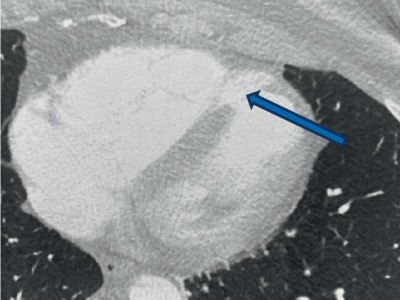

Bei einer Krebspatientin wird ein verdächtiger mediastinaler Lymphknoten bronchoskopisch biopsiert. Kurz darauf entwickeln sich erst ein Lymphknotenabszess, dann eine Blutstrominfektion – und weitere vier Wochen später schließlich multiple suspekte Läsionen im Gehirn. Der Blick in das Herz der 69-Jährigen zeigt, wie es dazu kommen konnte.

Fatale Komplikation nach Myokardinfarkt

Eine ältere Frau leidet tagelang unter zunehmender Atemnot, bis sie schließlich zum Notfall wird. Bereits präklinisch zeigen sich deutliche ST-Strecken-Hebungen, im Schockraum fällt ein lautes Systolikum auf, das Thorax-CT weist auf einen Kontrastmittelübertritt zwischen linkem und rechtem Ventrikel hin. Ihre Verdachtsdiagnose?

Jugendliches Mädchen bei EKG-Untersuchung/© Анна Ковальчук / stock.adobe.com (Symbolbild mit Fotomodell), Ventrikelseptumdefekt/© Fuhrmann J, Ratzenböck E doi.org/10.1007/s10049-024-01417-z unter CC-BY 4.0, Intrakranielle Abszesse/© Seidl H et al. doi.org/10.1007/s00108-025-01863-y unter CC-BY 4.0, Kind wird mit Stethoskop am Herzen abgehört/© Milan / stock.adobe.com, Reanimation im Rettungswagen/© herraez / stock.adobe.com (Symbolbild mit Fotomodell), Ultraschalluntersuchung am Herzen eines jungen Mannes/© H_Ko / Stock.adobe.com (Symbolbild mit Fotomodell), Frau mit Baby im Gespräch mit Ärztin/© SDI Productions / Getty Images / iStock (Symbolbild mit Fotomodellen), Ärztinnen und Ärzte im OP/© Svitlana / Stock.adobe.com (Symbolbild mit Fotomodellen), Seniorin steigt die Treppe hinab/© pomupomu / stock.adobe.com (Symbolbild mit Fotomodell), Messung der Sauerstoffsättigung/© Satjawat / stock.adobe.com (Symbolbild mit Fotomodellen), Rötlich-violette Papeln/© Dr.med.J.P.Müller / OKAPIA KG / / picture alliance (Symbolbild mit Fotomodell), Podcast - Diagnose: "Hirntod"/© [M] Dominik T. Schneider et al / all rights reserved Springer Medizin Verlag GmbH, Hände einer älteren Patientin/© hemvala40 / stock.adobe.com, Ärztin führt eine Nierenultraschalluntersuchung durch/© Graphicroyalty / stock.adobe.com (Symbolbild mit Fotomodell), Behandlungspfad: Leitsymptom Zyanose - Was sollte bei der Differenzialdiagnose bedacht werden?/© Springer Medizin Verlag GmbH, Search Icon, Herpes Zoster am Rücken/© Mumemories / Getty Images / iStock (Symbolbild mit Fotomodell), Junge Ärztin vor einem Triage-Zelt/© Milos / Stock.adobe.com (Symbolbild mit Fotomodell), DGIM Podcast-Reihe - Frailty/© (M) David L / peopleimages.com / Stock.adobe.com (Symbolbild mit Fotomodell), EKG befunden mit System - EKG Essential/© Springer Medizin Verlag GmbH